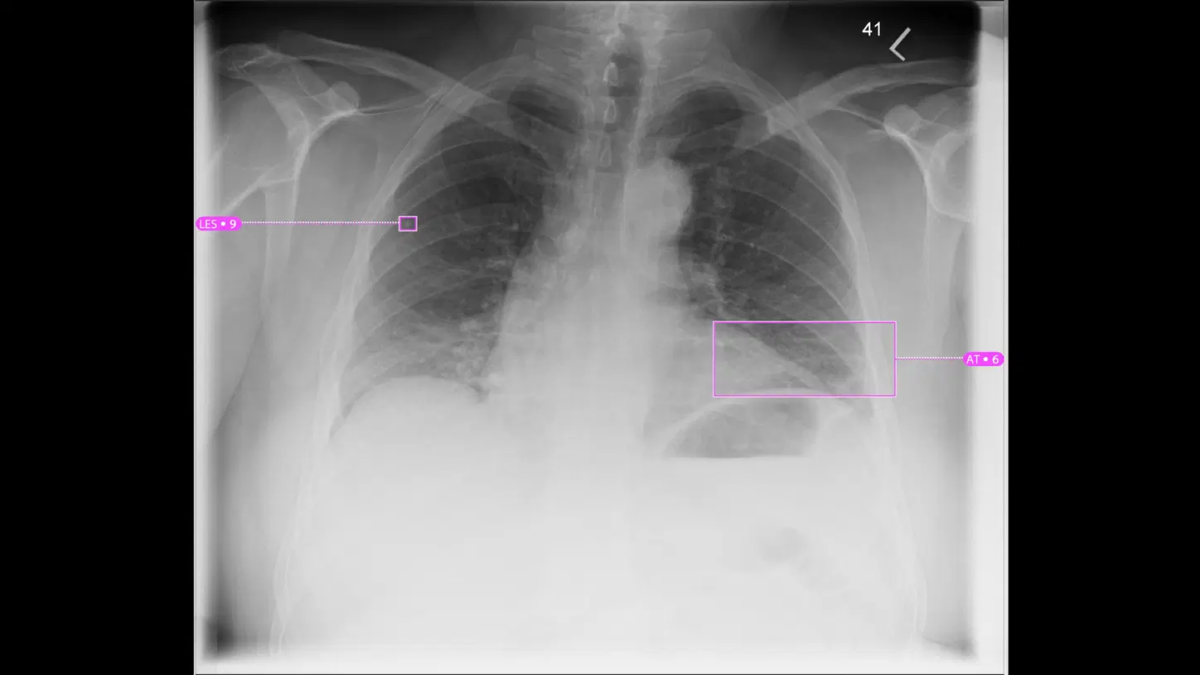

Chest radiography is an essential tool for detecting and managing cystic fibrosis, arming healthcare providers with valuable insights into lung health. A chest X-ray, performed using products like those offered through Siemens Healthineers, is often used in cystic fibrosis screening to identify structural changes such as mucus buildup, airway blockages, and lung infections. Even in cases where individuals experience mild symptoms, chest radiography can help detect early signs of the disease that might otherwise go unnoticed.

For those identified as a cystic fibrosis carrier, routine imaging plays a crucial role in monitoring lung function and tracking disease progression over time. By utilizing modern imaging technologies, healthcare providers can conduct comprehensive evaluations that support clinical decision-making and aid in developing personalized management strategies for individuals with cystic fibrosis.